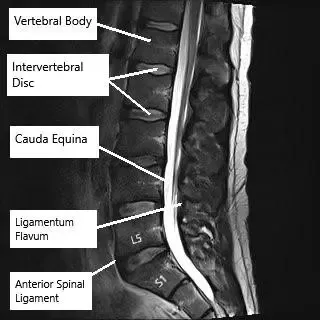

Resonancia magnética de la columna lumbar en corte axial y sagital

Resonancia magnética de la columna lumbar en corte axial y sagital.

Las radiografías proporcionan una visualización básica de la alineación de la columna vertebral y la integridad ósea. Los TAC ofrecen imágenes detalladas de las estructuras óseas y son útiles en traumatismos o afecciones degenerativas. La RM es la mejor herramienta de diagnóstico por imagen para evaluar los tejidos blandos, incluidos los discos intervertebrales, los ligamentos, las raíces nerviosas y la médula espinal.

La resonancia magnética también puede mostrar hernias discales, compresión nerviosa y cambios postoperatorios, como la colocación de una prótesis discal cervical, un implante que restablece el movimiento en un segmento vertebral enfermo.